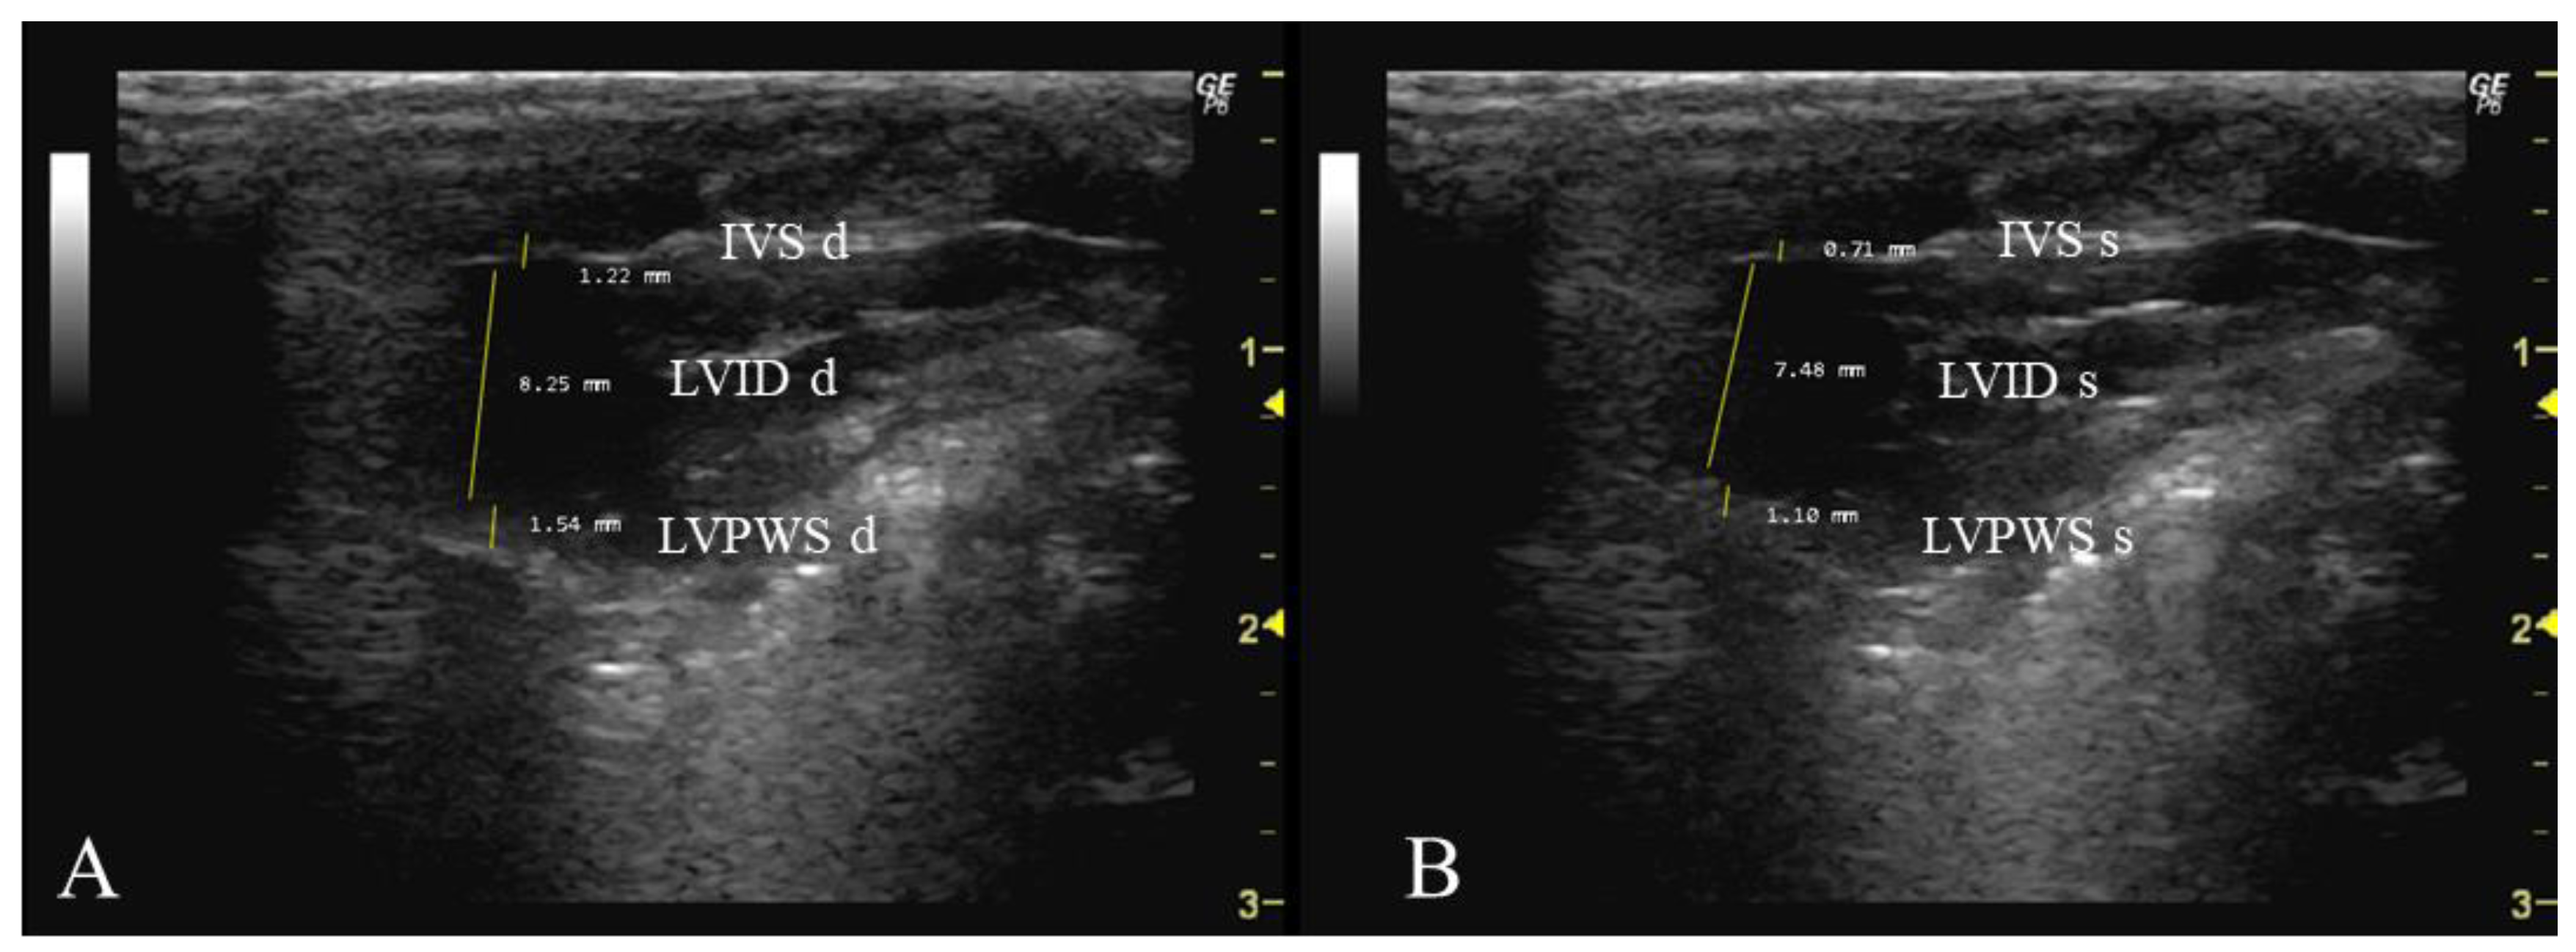

- How to measure IVS, LVID, and LVPW